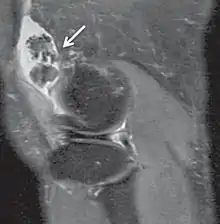

| Proton density weighted | PD | Long TR (to reduce T1) and short TE (to minimize T2).[7] | Joint disease and injury.[8]

|

![]() | |

Proton density

Proton density (PD)- weighted images are created by having a long repetition time (TR) and a short echo time (TE).[36] On images of the brain, this sequence has a more pronounced distinction between grey matter (bright) and white matter (darker grey), but with little contrast between brain and CSF.[36] It is very useful for the detection of arthropathy and injury.[37]